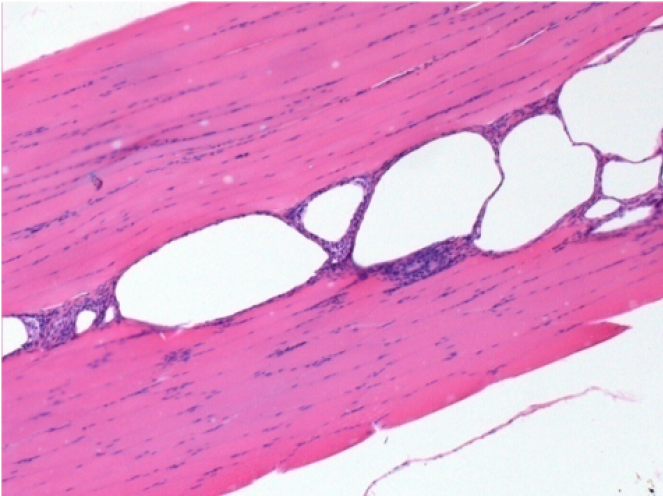

بعد شهر من حقن إندوبيل

بعد شهر واحد من حقن Endopeel 0.1 مل في العضلة أمام الظنبوب اليمنى.

ما يظهر باللون الأسود في الصور ليس نخرًا كما يتصور بعض العلماء!

في الواقع ، يجب أخذ 4 استنتاجات في الاعتبار :

- قطعة أثرية من التلوين

- عدم وجود نخر

- عملية بيولوجية

- موت الخلايا المبرمج

L : Control-100xD30

R:100xD30

R :400xD30